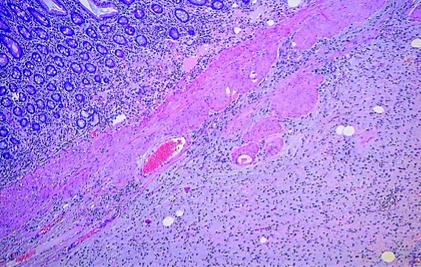

Immunohistochemical staining with anti-CD117 antibody – Positive expression in mast cells and negative expression in elongated spindle cells (Courtesy Dr. V. Penopoulos)